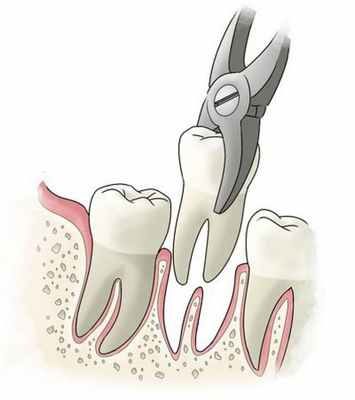

Некоторое время назад этот диагноз считался четким показанием для удаления зуба. Но, к счастью, возможности современной стоматологии позволяют врачам побороться с этой проблемой без радикальных мер.

Сегодня лечатся даже сложные виды периодонтита. Однако для успешности терапии требуются очень тщательный подход и умелые руки доктора. В нашей клинике вы найдете и то и другое.